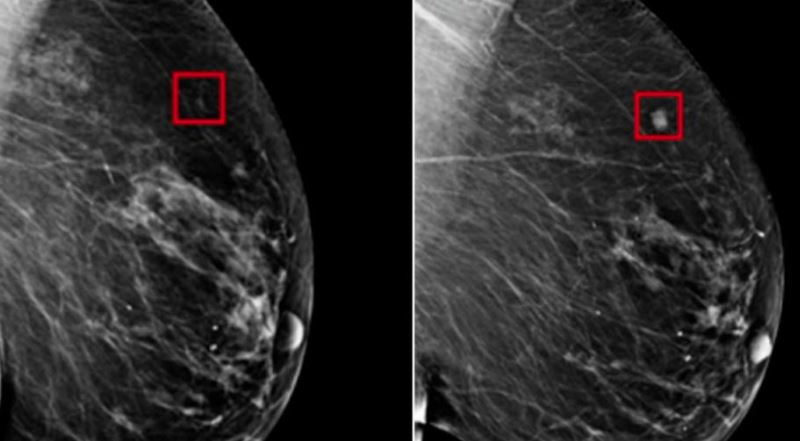

Προηγουμένως, δύο άλλοι ακτινολόγοι της είχαν πει ότι η ακτινογραφία δεν έδειχνε σημάδια ότι η ασθενής πάσχει από καρκίνο του μαστού. Αλλά η Δρ. Αμπροζάι είχε εστιάσει πολύ προσεκτικά σε διάφορες περιοχές της ακτινογραφίας που είχαν επισημανθεί με κόκκινους κύκλους, τις οποίες ένα λογισμικό τεχνητής νοημοσύνης είχε επισημάνει ως δυνητικά καρκινικές.

Μέσα από τα εκατομμύρια των περιπτώσεων με τα οποία τροφοδοτείται το σύστημα, αυτή η τεχνολογία δημιουργεί μια μαθηματική αναπαράσταση των “κανονικών” μαστογραφιών και εκείνων με καρκίνο. Με την ικανότητα να βλέπει κάθε εικόνα με πιο λεπτομερή τρόπο από το ανθρώπινο μάτι, στη συνέχεια συγκρίνει αυτά τα πρότυπα που έχει για να βρει ανωμαλίες σε κάθε μαστογραφία.

Πέρσι, μετά από την εξέταση σχεδόν 275.000 περιπτώσεων καρκίνου του μαστού, η Kheiron ανακοίνωσε ότι το λογισμικό της έφτασε σε επιτυχία τις επιδόσεις των γιατρών ακτινολόγων, μόνο όμως όταν ενεργούσε ως ο δεύτερος αναγνώστης σαρώσεων των μαστογραφιών.

Επίσης, μείωσε τον φόρτο εργασίας των ακτινολόγων κατά τουλάχιστον 30%, επειδή μείωσε και τον αριθμό των ακτινογραφιών που χρειάζονταν για να μελετήσουν. Σε άλλα αποτελέσματα που ήρθαν από μια ουγγρική κλινική πέρσι, η τεχνολογία αύξησε το ποσοστό ανίχνευσης καρκίνου κατά 13%, επειδή εντοπίστηκαν περισσότεροι κακοήθεις όγκοι.

Ο Δρ Τάμπαρ, του οποίου οι τεχνικές ανάγνωσης μαστογραφίας είναι αυτές που συνήθως χρησιμοποιούνται και από τους περισσότερους ακτινολόγους, δοκίμασε το λογισμικό το 2021 πάνω σε κάποιες από τις πιο δύσκολες περιπτώσεις της καριέρας του, στις οποίες οι ακτινολόγοι δεν είχαν προσέξει τα σημάδια ενός αναπτυσσόμενου καρκίνου. Και σε όλες αυτές τις περιπτώσεις, η τεχνητή νοημοσύνη κατάφερε να τα εντοπίσει.